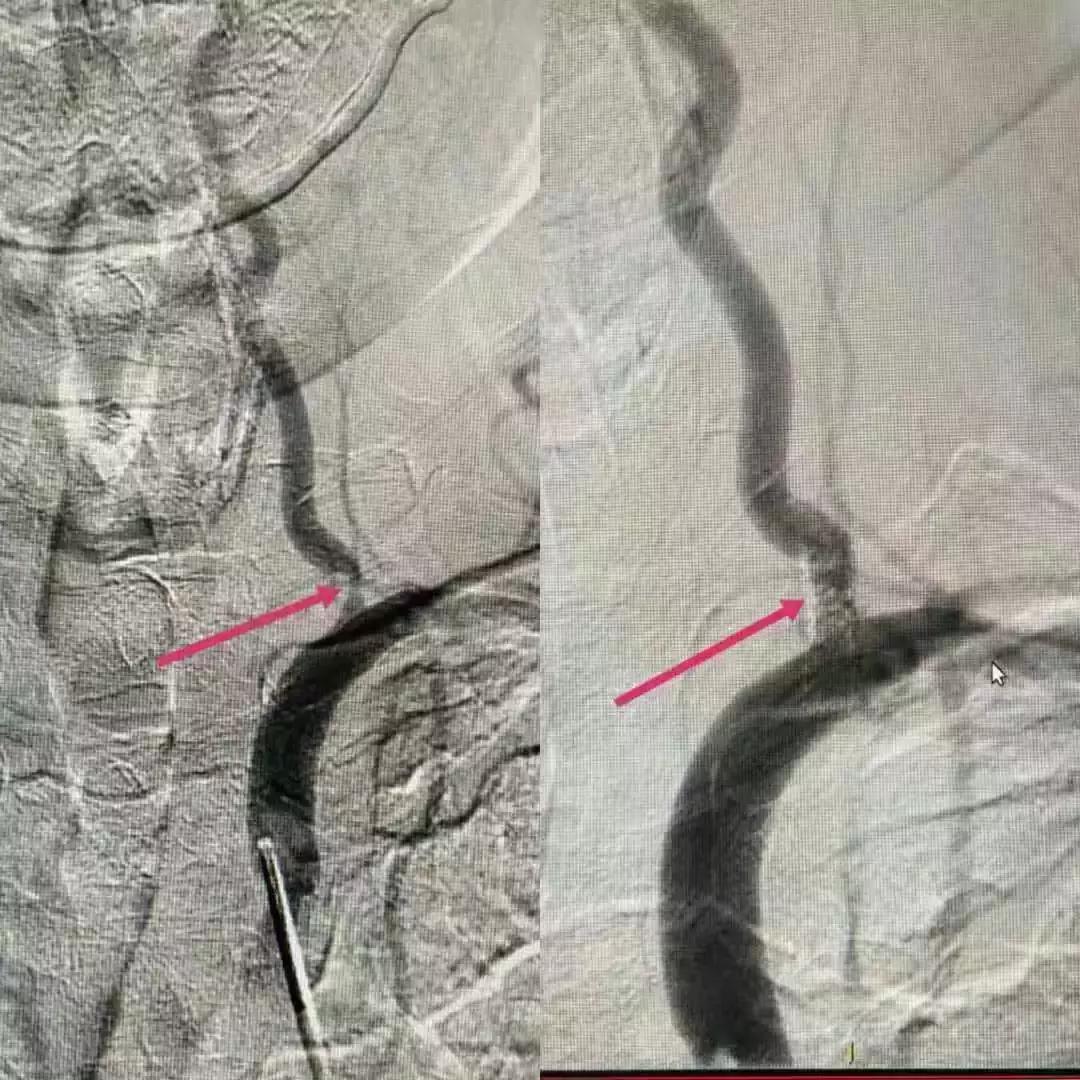

11月5日,我们针对患者手术险、急放药品的准备、术后患者的护理等进行讨论,护士长也积极参加,为术后患者的护理也做着准备,并且认真的标记出需关注的事项,以备对护理人员进行培训。11月6日中午,我们全部人员待命,手术持续一个半小时后于14:40顺利完成左侧颈内动脉、左侧椎动脉支架植入。支架植入术后,患者血管狭窄处管径基本恢复正常,血流通畅,脑灌注良好,患者头量症状消失,术后留院观察期间未再出现肢体麻木无力症状。